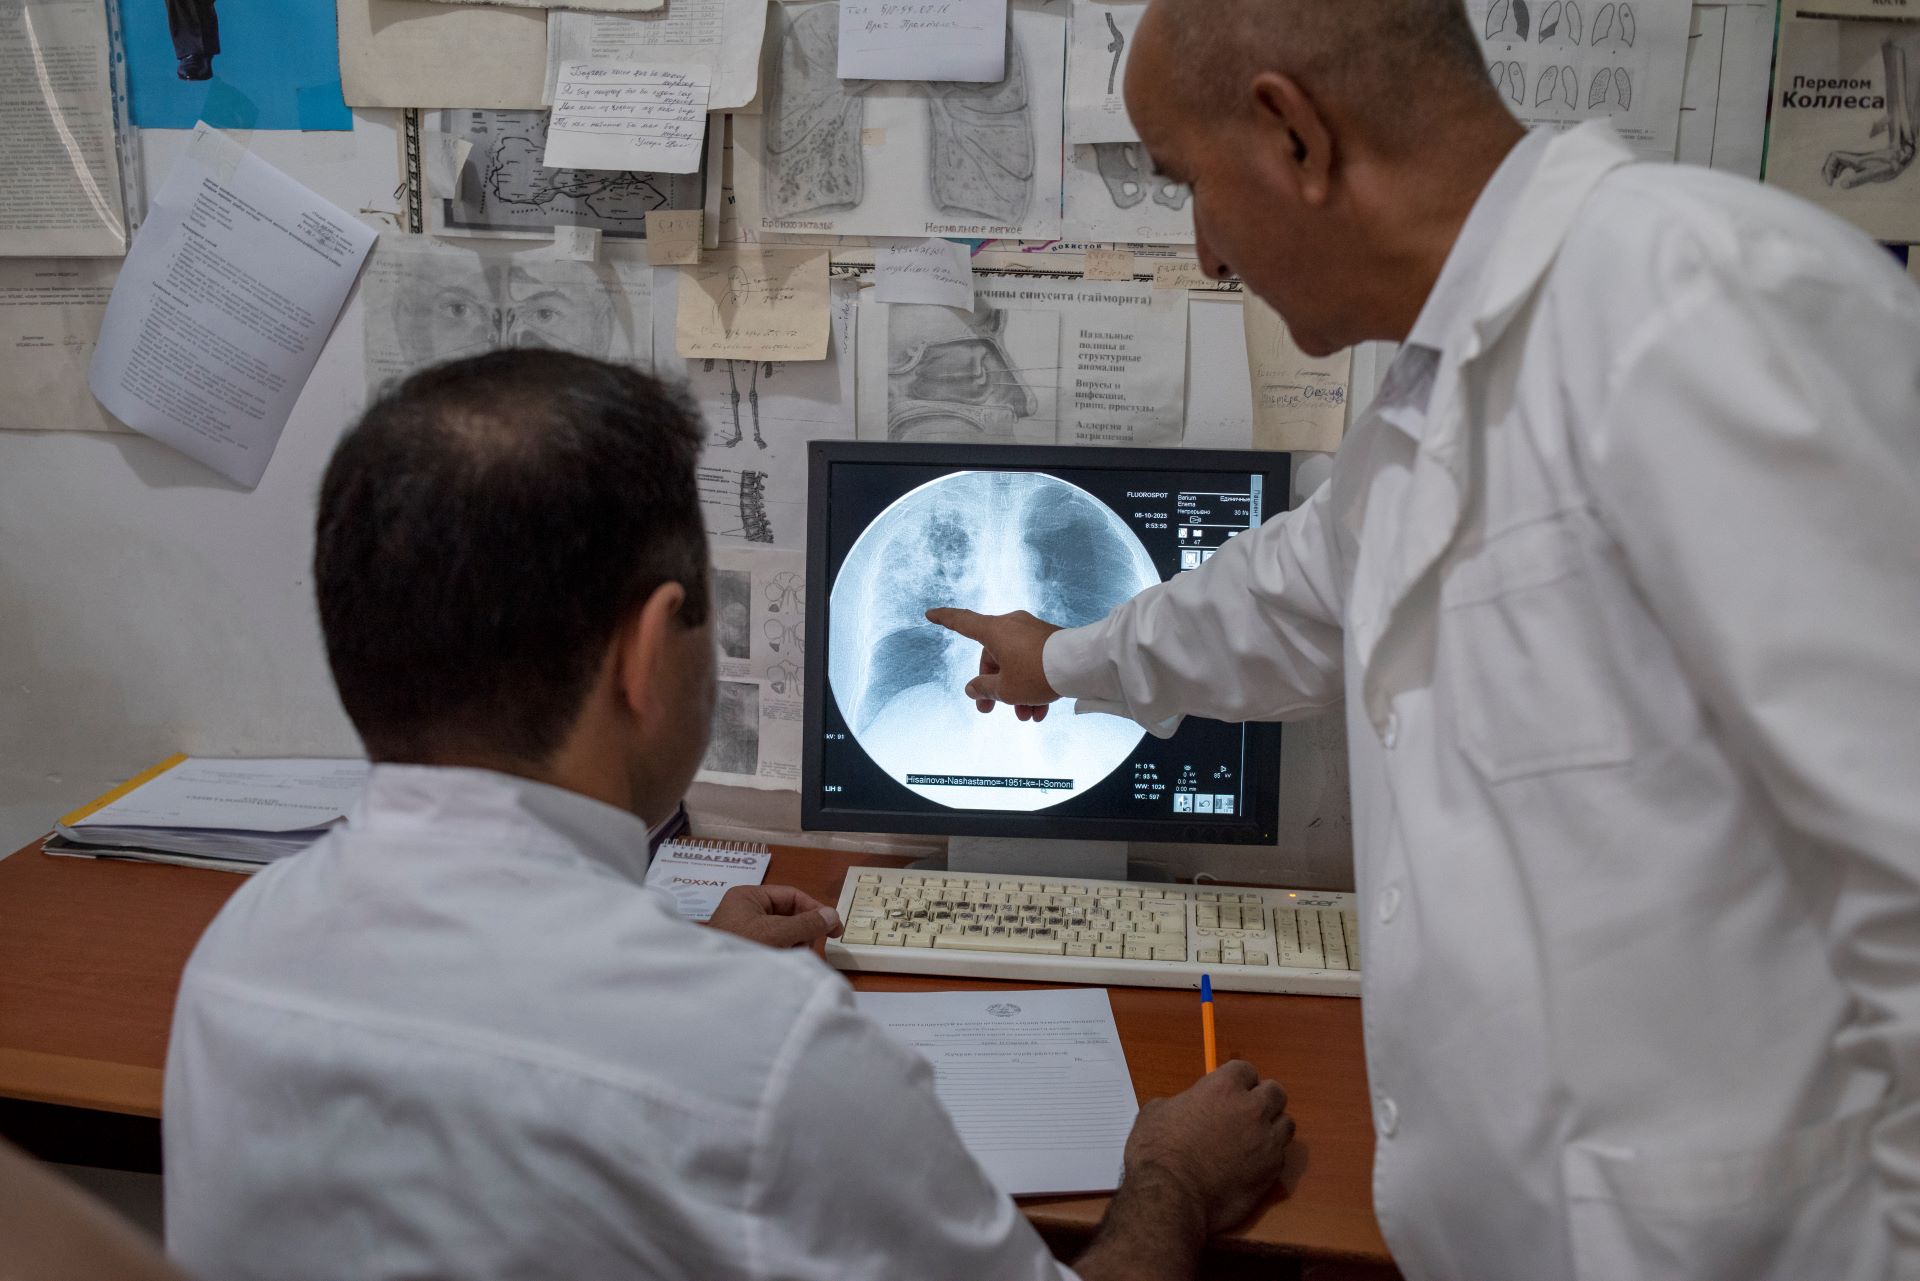

Tuberculosis